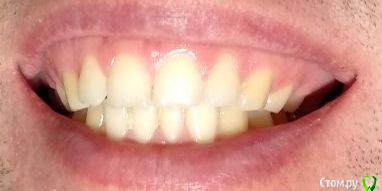

Здравствуйте! Откололся кусок зуба. 8 октября сделали КЛКТ (3Д снимок всех зубов). Вскрыли зуб, была проведена девитализация. Поставили диагноз: хронический фиброзный пульпит 37 зуба. 18 октября было проведено первичное лечение 3-х канального зуба эндомотором с использованием микроскопа и системы коффердам. Все каналы были запломбированы гуттаперчивыми штифтами на силлере методом латеральной конденсации Adseal, внутрь заложена ватка и поставлена временная пломба дентин-паста. 29 октября ортопед №1 посмотрел прицельный снимок (см. снимок зуба 2) и сам зуб, пломбу не снимал. Озвучил, что у меня низкая высота зуба, мне нужно установить культевую кобальт-хромовую вкладку и сверху покрыть металлокерамической коронкой зуб. Также сказал, что циркониевая вкладка мне не подходит из-за высоты. Однако, поскольку ортопед №1 уходил на обучение, мне было предложено обратиться в другую клинику к другому ортопеду. 1 ноября ортопед №2 посмотрев мой зуб без снимка заявил, что у меня сохранились три стенки у зуба и мне надо просто закрыть пломбой этой зуб. Поскольку ортопед №2 предложил диаметрально противоположное лечение зуба, то я решил обратиться в третью клинику. Ортопед №3 посмотрев снимок моего зуба, сам зуб, в том числе внутри (снял мою временную пломбу из дентина), заявил, что у меня низкая высота зуба и мне нельзя ставить культевую вкладку и коронку. И было предложено сделать вкладку из пресс керамики overlay. Также когда удалили временную пломбу у меня увидели кариес на этом зубе. В конце приема мне взамен снятой пломбы установили временную пломбу парасепт.

Сделал несколько фотографий, тк не совсем понял с какого ракурса делать фото с сомкнутыми зубами.